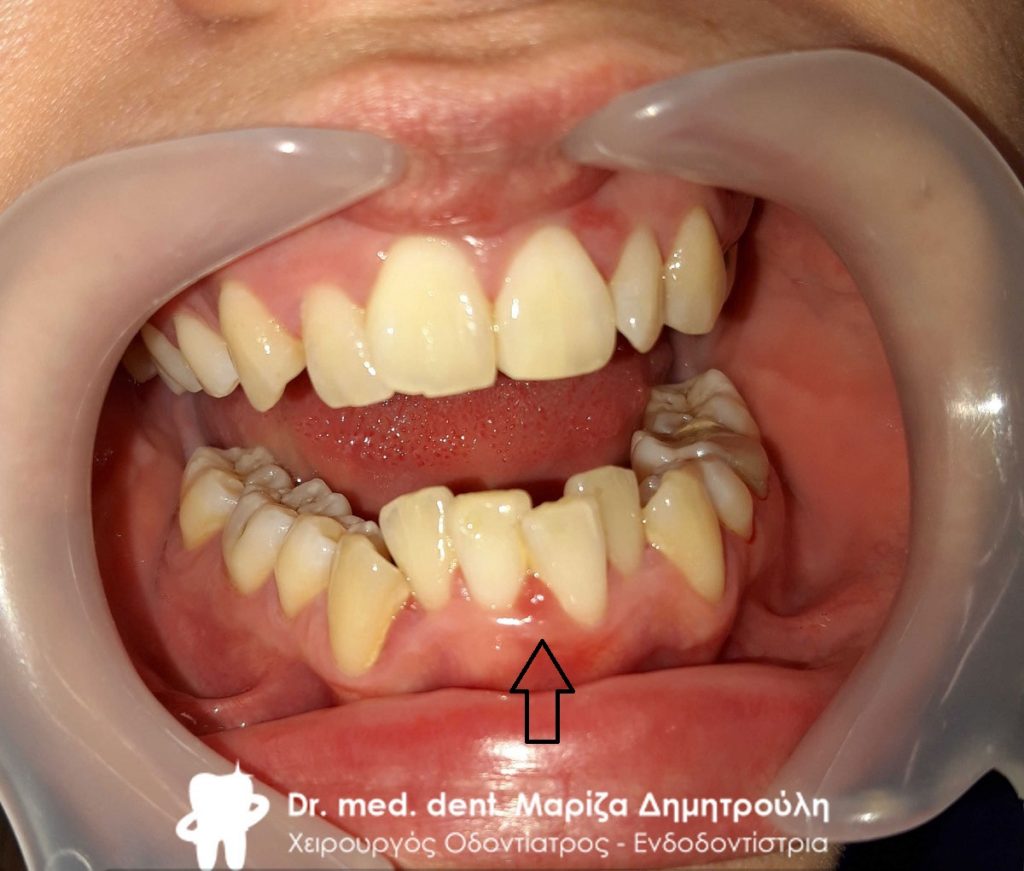

Εικόνα της επουλίδας μετά τη θεραπεία της ουλίτιδας κύησης

Η επουλίδα κύησης είναι ενοχλητική για τις εγκύους, έχει κόκκινο χρώμα και  μοιάζει σαν σπυράκι χωρίς κεφάλι.Το θετικό είναι οτι το ογκίδιο αυτό δεν είναι ανησυχητικό, καθώς είναι τελείως ανώδυνο και ακίνδυνο. Συνήθως η επουλίδα κύησης εξαφανίζεται αμέσως μετά την εγκυμοσύνη, χωρίς να αφήνει κάποιο υπόλειμμα. Αν η επουλίδα παραμένει και δεν υποχωρεί μετά την εγκυμοσύνη, τότε η γυναίκα θα πρέπει να απευθυνθεί στον οδοντίατρο για την αφαίρεση της.